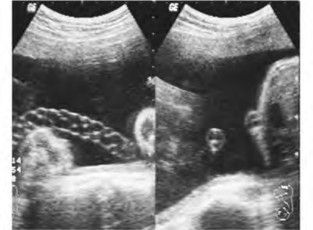

指脐带内只有一条脐动脉和一条脐静脉,发病率约1%(图34-22A、B)。

图34-22A 胎儿单脐动脉异常声像图

(1)脐带多切面显示仅有两个血流断面,一个为脐静脉,一个为脐动脉,脐动脉较正常扩张,内径可与脐静脉相等。

图34-22B 单脐动脉呈麻花状二维与彩色多普照勒超声图(见彩图47)

(2)单一切面和单一部位显示单脐动脉要慎重,有假阳性出现,应多切面和多部位及多普勒超声进行补充检查。